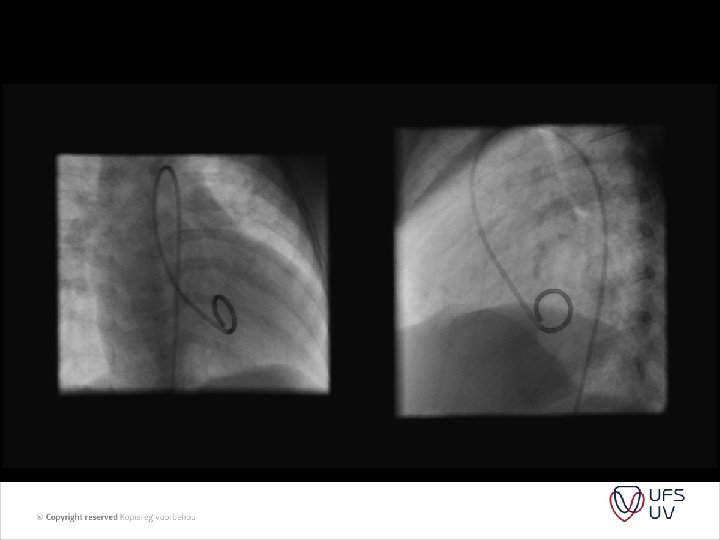

PVR = PAP/ PAflow Substitude PA pressure with TR jet Substitude PA flow by RVOT VTI (velosity time integral) And we get PVR = TR jet velocity/ RVOT VTI x 10

• • Figure 1 Images showing peak tricuspid regurgitant velocity (TRV) and right ventricular outflow time-velocity integral (TVIRVOT) in a patient with normal pulmonary vascular resistance (PVR). (A) TRV is 2. 86 m/s. (B) TVIRVOT is 20. 8 cm. The ratio of TRV/TVIRVOT = 2. 86/20. 8 = 0. 1375. . This patient’s invasive PVR measurement was within 0. 4 WU of the echocardiographic value (PVRCATH = 1. 3 WU). PVRECHO = PVR in WU calculated based on the linear regression equation in which a value for PVR in WU was modeled based on TRV/TVIRVOT. PVRCATH = invasive PVR.

• Figure 2 Images showing TRV and TVIRVOT in a patient with elevated PVR. (A) TRV is 3. 64 m/s. (B) TVIRVOT shows a clear deceleration of pulmonary flow before the pulmonic valve closure click and is calculated at 6. 5 cm. The ratio of TRV/TVIRVOT = 3. 64/6. 5 = 0. 56. . This patient’s invasive PVR measurement is also within 0. 4 WU of the echocardiographic value (PVRCATH = 6. 0 WU). Abbreviations as in Figure 1. • • J Am Coll Cardiol, 2003; 41: 10211027